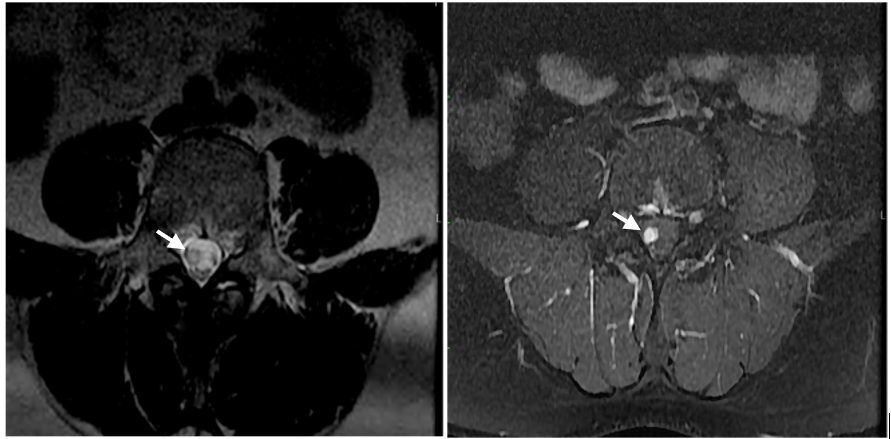

Figure 3: Axial T2 weighted image.

Figure 4: Axial Contrast+ image.

MRI is the diagnostic modality of choice due to its noninvasive nature and high accuracy on spinal tumours. The critical MRI indicators for spinal schwannomas include:

Signal intensity that is equal or less than that of spinal cord on T1 weighted images and a mild to marked hyperintensity on T2-weighted images. Focal areas of even greater hyperintensity on T2-weighted images often correspond to cystic regions, whereas hypointensity may represent hemorrhage, dense cellularity, or collagen deposition [2.3]. Virtually, 100% enhance on T1 C+.